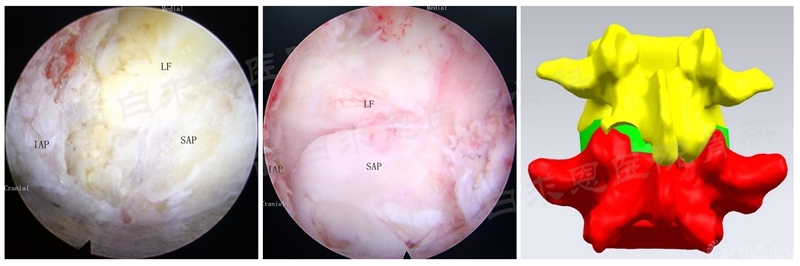

(3)下关节突成形

SAP:Superior articular process(下关节突);IAP:Inferior articular process(上关节突);LF:Ligamentum flavum(黄韧带)

(4)上关节突成形

N:Nerve root(神经根);Disc(椎间盘)